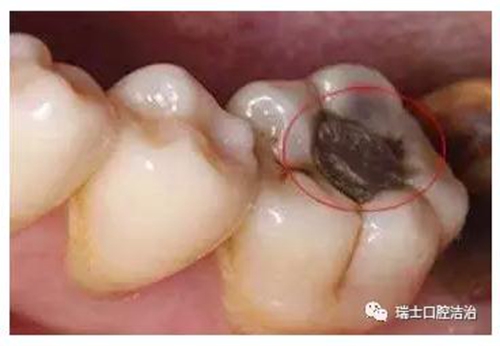

齲齒對兒童牙齒的損害不容忽視,國際上已經(jīng)將齲齒、腫瘤以及心血管疾病列為危害人類健康的三大疾病。齲齒是牙齒在多種因素影響下,牙硬組織脫礦、有機質(zhì)溶解、牙組織進行性破壞,導(dǎo)致牙齒缺損的常見疾病。

兒童作為預(yù)防齲齒的重點人群,家長必須引起足夠的重視。家長要隨時留意孩子的牙齒情況,尤其是后磨牙,比如孩子的第一顆恒牙六齡齒(下頜)就是很容易發(fā)生齲齒的牙齒。一旦發(fā)現(xiàn)齲齒,就必須及時治療,不要心存僥幸,也不能輕視齲齒的破壞力。齲齒可完全破壞整個牙冠,僅殘留半截壓根暴露在外,黑乎乎的很是嚇人。